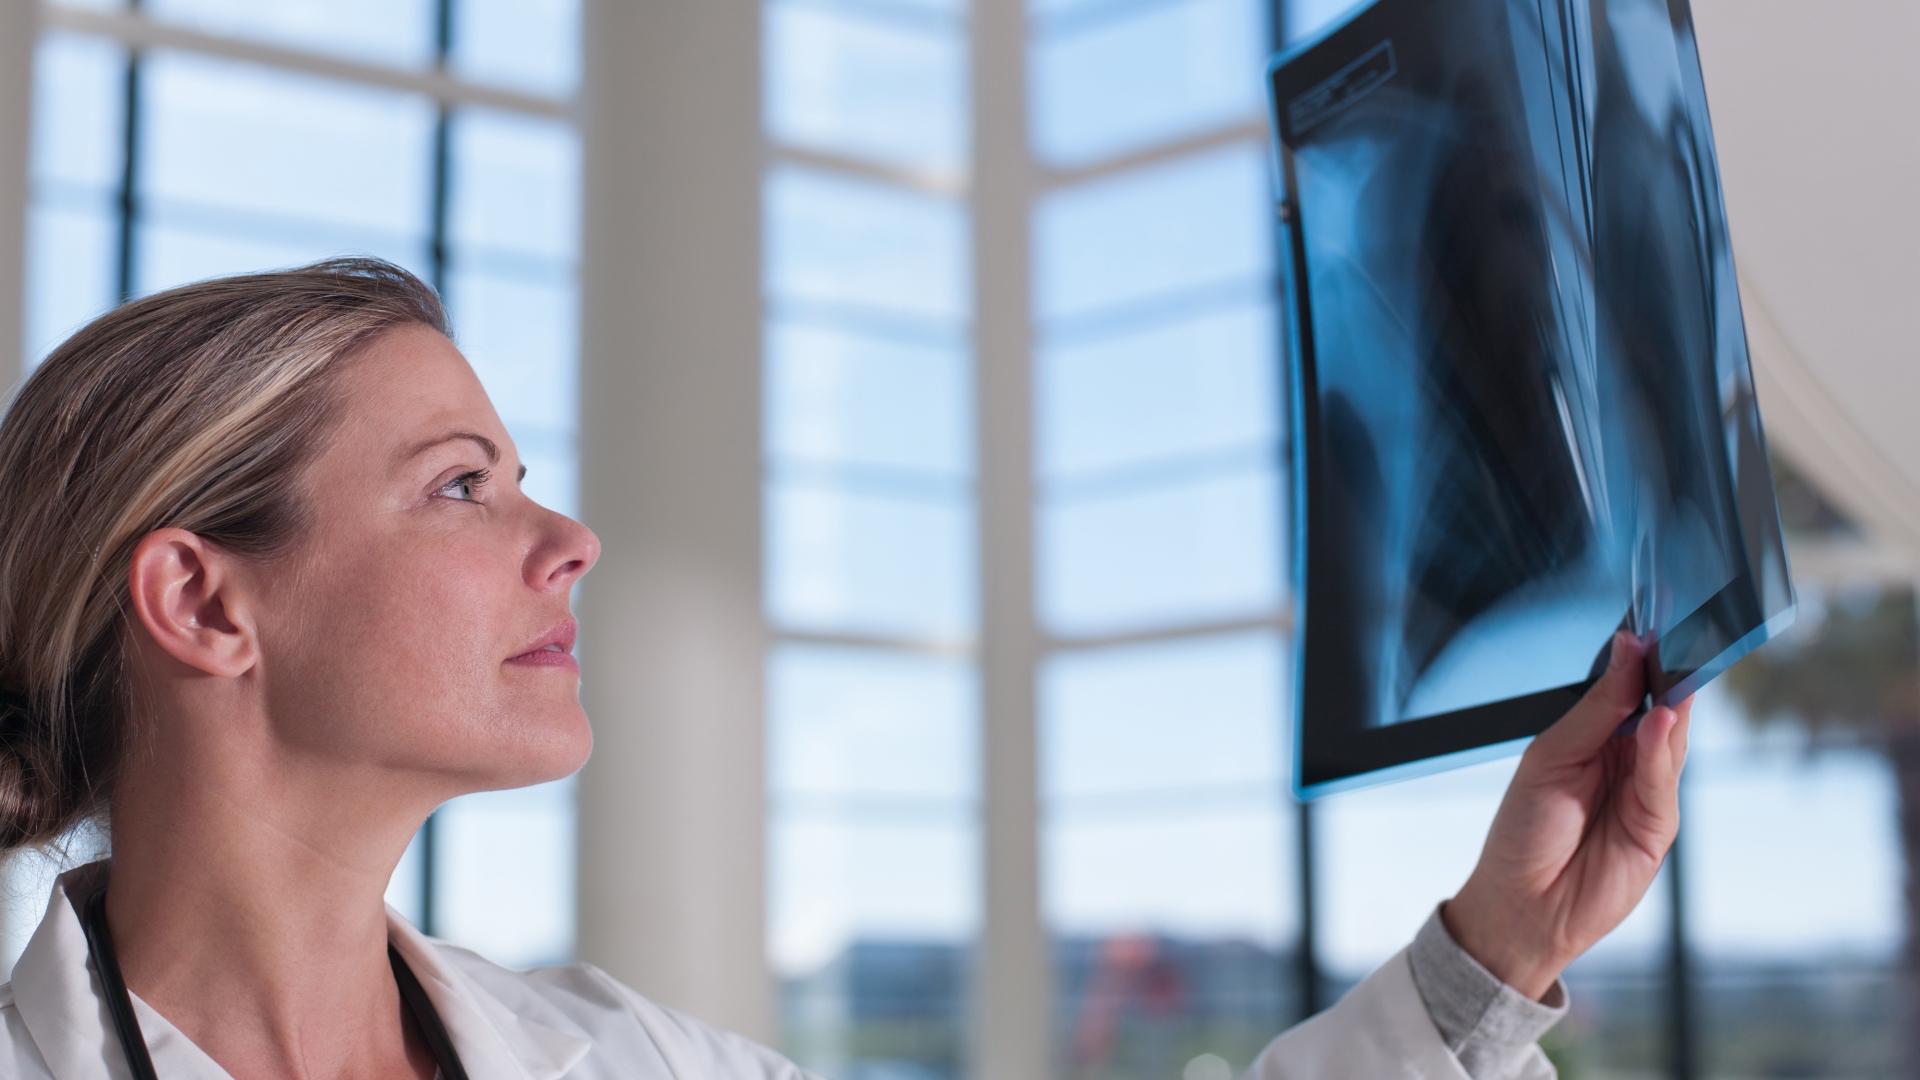

Ha felmenőid között volt daganatos beteg, mindenképp menj el ezekre a vizsgálatokra

A daganatos betegségek esetén ritka, hogy öröklődés állna a háttérben, de azért érdemes elmenni bizonyos szűrővizsgálatokra, ha a felmenők között előfordult rákbeteg.

„A mellrák után az életem sokáig még a vizsgálatokról szólt”

A mellrák gyógyulási folyamata nemcsak a műtétből, kemoterápiából és sugárkezelésből áll, hanem utána még öt évig rendszeresen szigorú kontrollvizsgálatokra kell járni.

Mihály vagyok, mellrákkal küzdök

2012-t írtak, amikor Mihály felfedezett egy csomót a bal mellében. Háziorvosához fordult, aki azonnal közölte a 46 éves tanítóval, hogy további vizsgálatokra lesz szüksége. Amikor nem sokkal később a férfi meghallotta a diagnózist, nem akart hinni a fülének, korábban abban a hitben élt, hogy a mellrák „női” betegség.

Ezekre a szűrésekre lenne szükségük a férfiaknak

Nemtörődömség, félelem, ‘amiről nem tudok, az nem fáj’ attitűd: számtalan magyarázata lehet annak, hogy a férfiak miért nem járnak szűrővizsgálatokra – pedig, ahogy a nőket, úgy az erősebbik nem képviselőit is utolérheti megannyi baj, aminek jelentős részét időben ki lehetne szűrni. Cikkünkben azokat a vizsgálatokat gyűjtöttük össze, ami minden férfinak ajánlott lenne – nem csak maga, de szerettei miatt is.